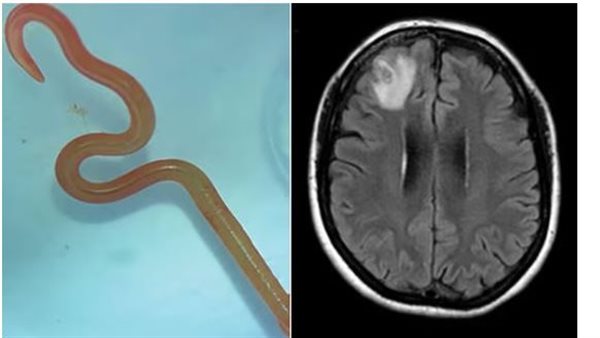

ونقلت صحيفة الجارديان البريطانية تفاصيل الواقعة، حيث اشتكت امرأة من النسيان والاكتئاب قبل أن يخرج الأطباء دودة مستديرة بطول 8 سم توجد عادة في الثعابين ليصبح هذا الاكتشاف هو الأول من نوعه في العالم.

واستخرجت جراحة الأعصاب، الدكتورة هاري بريا باندي، دودة طفيلية طولها 8 سم من مريضتها، مما دفعها إلى استدعاء سيناناياكي وزملائها الآخرين في المستشفى للحصول على المشورة بشأن ما يجب القيام به بعد ذلك.